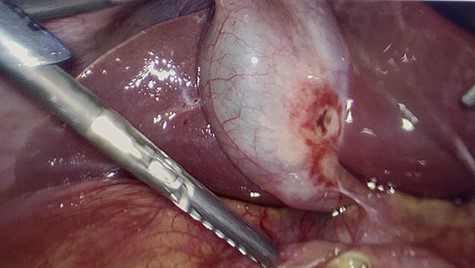

All of the standard preoperative measures were taken and the patient was prepped and draped for laparoscopic cholecystectomy. Ports were placed in a typical fashion for this operation, with A 12 mm Hasson trocar placed in a supraumbilical position, and 5 mm trocars placed in the epigastrium and RUQ x2. Upon insertion of the laparoscope, the uterus was still large in the pelvis and there was a small amount of bloody fluid in the abdomen. The fundus of the gallbladder was grasped and retracted cephalad. With this maneuver it appeared that the duodenum had fused itself to the infundibulum of the gallbladder. Upon gently peeling the duodenum off of the gallbladder, it became obvious that there was a perforated duodenal in the first portion of the anterior duodenum and had been the gallbladder that sealed the perforation (Figs 4–6). The gallbladder showed signs of erosion at the site where it patched the duodenum as well (Fig. 6). At this time we proceeded with laparoscopic cholecystectomy first, prior to addressing the duodenum. Once successfully completed with the cholecystectomy, we performed a laparoscopic graham patch with our existing ports, which can be seen in Fig. 7. A #10 flat JP was inserted in the region of the graham patch. The abdomen was irrigated and then suctioned clean. The repair was confirmed by placing underwater with the second portion of the duodenum compressed, while anesthesia insufflated the stomach/duodenum through an OG tube. The patient tolerated the operation well, extubated, and transported to recovery.

First portion of duodenum with perforated ulcer. Gallbladder retracted out of frame.